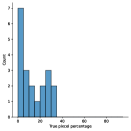

A few sample images and the corresponding masks of the polyp dataset in HyperKvasir are shown in Fig 2. The polyp images are RGB images. The masks of the polyp images are single-channel images with white () for true pixels, which represent polyp regions, and black () for false pixels, which represent clean colon or background regions. In this dataset, there are different sizes of polyps. The distribution of polyp sizes as a percentage of the full image size is presented in the histogram plot in Fig 3, and we can observe that there are more relatively small polyps compared to larger polyps. Additionally, a subset of this dataset was used to prove that the performance of segmentation models trained with small datasets can be improved using our SinGAN-Seg pipeline, and the whole dataset was used to show the effect of using SinGAN-Seg generated synthetic images instead of a large dataset which has enough data to train segmentation models. In this regard, this dataset was used for two purposes:

To understand the difference between the mask distribution of real images and synthetic images, we plotted pixel distribution of masks of synthetic images in Fig 6. This plot is comparable to the pixel distribution presented in Fig 3. The randomness of the generations made differences in the distribution of true pixel percentages compared to the true pixel distribution of real masks of real images. However, the overall shape of synthetic data mask distribution shows a more or less similar distribution pattern to the real true pixel percentage distribution.